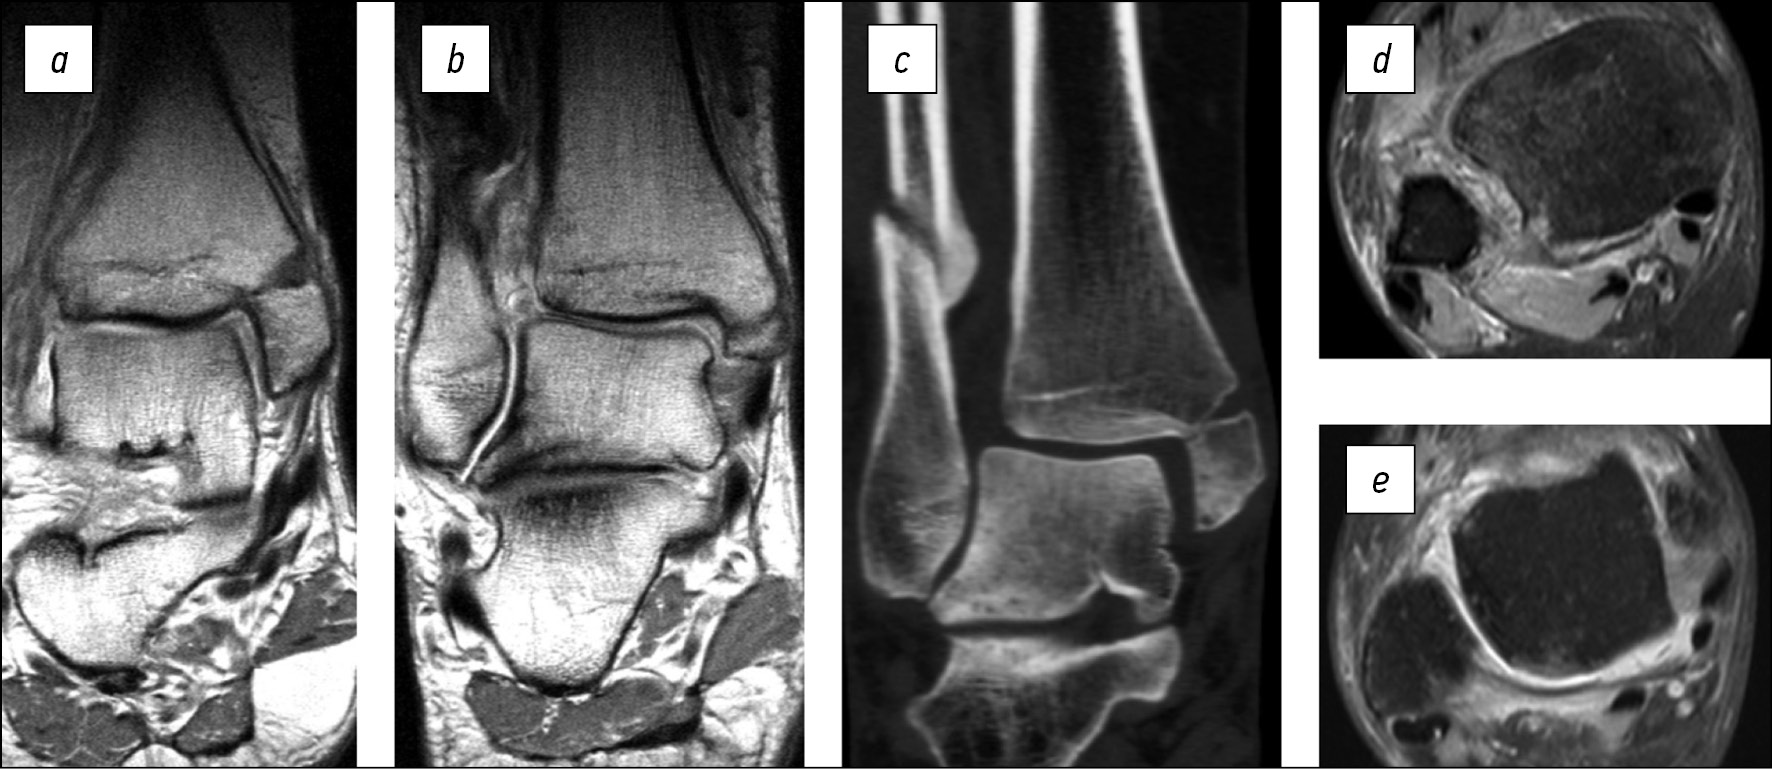

На МРТ правого голеностопного сустава во фронтальной плоскости в режиме Т1 через 6 месяцев после оперативного вмешательства наблюдаются зрелые рубцы, соответствующие по длине и позиции поверхностной (рис. 3a) и глубокой (рис. 3b) порциям внутренней коллатеральной связки. На МРТ в аксиальной плоскости в режиме Т2 наблюдаются зрелые рубцы, соответствующие по длине и позиции межберцовым связкам (рис. 3c) и глубокой порции внутренней коллатеральной связки (рис. 3d).

Рис. 3. Магнитно-резонансные томограммы пациентки В. через 6 месяцев после оперативного вмешательства: a, b — во фронтальной плоскости в режиме Т1, c, d — в аксиальной плоскости в режиме Т2

Fig. 3. 6 months postoperative magnetic resonance imaging of patient B.: a, b — T1 in coronal plane, c, d — T2 in axial plane

На рентгенограммах голеностопного сустава в прямой (рис. 7a) и боковой (рис. 7b) проекциях при поступлении наблюдаются подвывих стопы кнаружи, отрывной перелом переднего и заднего бугорков малоберцовой вырезки большеберцовой кости со смещением отломков. МРТ голеностопного сустава в аксиальной плоскости в режиме Т1 (рис. 7с) подтверждает данные рентгенографии, во фронтальной плоскости в режиме Т2 (рис. 7d) демонстрирует наличие трабекулярного отёка дистального метаэпифиза большеберцовой кости, блока таранной кости, тела пяточной кости.

Рис. 7. a — рентгенограмма пациента П. при поступлении в прямой проекции, b — рентгенограмма в боковой проекции, c — магнитно-резонансная томограмма в аксиальной плоскости в режиме Т1, d — магнитно-резонансная томограмма во фронтальной плоскости в режиме Т2

Fig. 7. Preoperative X-rays of patient P.: a — A-P-view, b — lateral view, c — axial T1 magnetic resonance imaging, d — coronal T2 magnetic resonance imaging